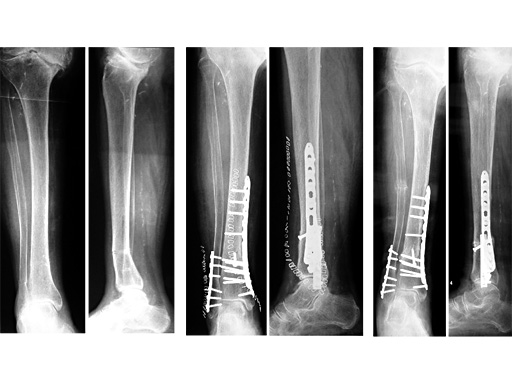

LCP Distal Tibia Plate

The Distal Tibia Plate is anatomically pre-shaped and locked screws provide angular stability. In the shaft area this plate has a standard dimension and a limited contact profile, more distally the plate gets thinner to spare the delicate soft tissues over the medial tibia. It is of special advantage in osteoporotic bone, where the anatomical design supports the reduction and allows percutaneous application. Indications are extra- and intra-articular fractures of the distal tibia (43 A1 to A3 and C1 to C3), especially with osteoporotic bone and/or with injury to the overlying soft tissues. The Distal Tibia Plate is available in Stainless Steel and Titanium, they are fully compatible with all 3.5 conventional screws, with the 3.5 Locking Compression Plate System and with the Calcaneus Locking Plate Set.

89y -f- accident 07/01, strong Osteoporosis